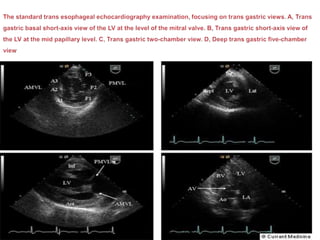

 With the transducer tip in fundus of the stomach (about 40-45cm from the

incisors)

 The transducer array at 0 degree produces the short –axis view of LV

and RV.

 Anteflexion or slight withdrawl of the tip of transducer optimizes the basal

short-axis view of the ventricles.

 Retroflection of tip produces more apical short-axis view.

 Sequential rotation of multi plane transducer provides the primary

trans gastric views of the LV

 0 degree, short-axis view of LV and RV

 70-90 degree- longitudinal two-chamber view of the LV

 110-135 degree- trans gastric view of the LVOT and aortic valve